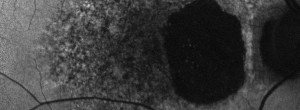

Ensayo clínico OAKS-DERBY: Eficacia y seguridad de pegcetacoplan en el tratamiento de la atrofia geográfica secundaria a DMAE